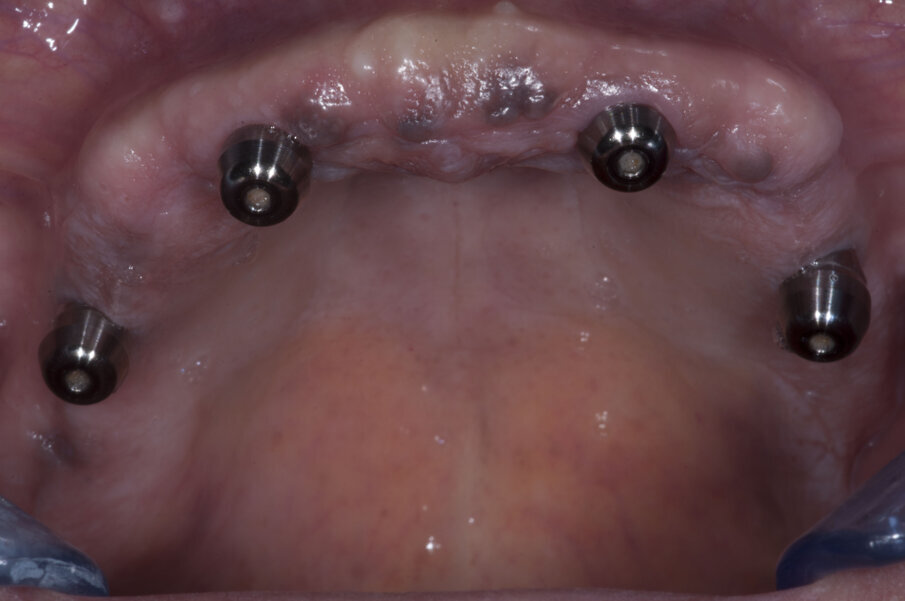

La paziente A. S. di anni 67 si presentata in visita richiedendo la sostituzione della protesi totale superiore con una nuova protesi, possibilmente fissa (Figg. 1-3). Essendo l’anamnesi negativa si è proceduto allo studio e alla pianificazione del caso. La paziente si è presentata con una OPT delle arcate dentarie (Fig. 4) che evidenziava un’ottima quantità di osso alveolare residuo. Dopo esame intra- orale si prescrive una CBCT per poter pianificare nel dettaglio la chirurgia implantare.